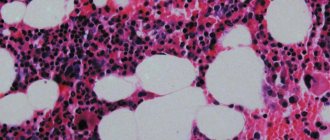

Липидограмма представляет собой расширенный биохимический анализ крови, включающий липидный спектр и отражающий содержание общего холестерина, липопротеинов высокой и низкой плотности, а также триглицеридов. Кроме того, по данному анализу определяется соотношение этих показателей. Одним из основных показателей липидограммы является общий холестерин. Он отражает суммарное содержание в крови такого вещества, как стерол.

Общий уровень холестерина отражает риск образования атеросклеростических бляшек

Количество ЛПОНП служит показателем уровня вредного холестерола и липидного обмена. Избыточный холестерин откладывается на стенках сосудов. Сначала на них образуется налет, а со временем формируются бляшки. Переизбыток холестерина также может оказывать негативное влияние на транспорт триглицеридов. Результаты тест оцениваются с учетом клинической картины и данных других исследований.